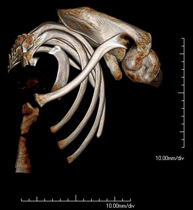

Exploración radiológica que mediante un sistema de rayos X y detectores que giran alrededor del paciente, reconstruyendo las imágenes por ordenador, permite el estudio detallado de la parrilla costal. - Angio-TC Cardíaco o TC Cardíaco

Exploración radiológica que mediante un sistema de rayos X y detectores que giran alrededor del paciente, reconstruyendo las imágenes por ordenador (TC Multidetector), permite el estudio de huesos, músculos y articulaciones de la pelvis. - TC de malucs